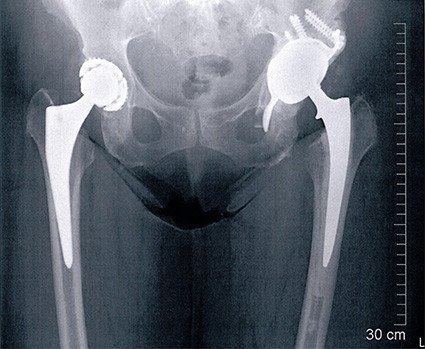

Bei der Revisionsoperation mussten wir feststellen, dass die Hüftmuskulatur grösstenteils vernarbt und nicht mehr funktionsfähig war. Dies war der Hauptgrund sowohl der Luxationen als auch des erneuten Pfannen-Versagens. Wir haben daher eine Pfanne gewählt, welche gegen Ausrisse relativ resistent ist (eine sogenannte Burch-Schneider-Schale). Diese Schale weist im unteren Bereich einen langen Flansch auf, welcher in den Knochen eingeschlagen wird. So kann sie schwierig ausreissen. Die Schale wurde in die eigentliche Pfanne einzementiert, wobei es sich um eine Prothese mit einer zweifachen Mobilität handelt. D. h. es bewegt sich sowohl der Kopf in der Polyethylen-Pfanne als auch die Polyethylen-Pfanne in der Aussenschale. Dies führt zu einer grossen Luxationssicherheit.

Die funktionsunfähige Muskulatur haben wir partiell verbessert, indem wir das Bein verlängert und durch die Verwendung eines Spezialkopfes die Beinachse möglichst an den Körper herangenommen haben. Die Patientin ist mit dem Verlauf zufrieden. Zwar ist sie auf die Benützung eines Stockes angewiesen, aber schmerzfrei. Sie hat ein stabiles Gefühl in dieser linken Hüfte.